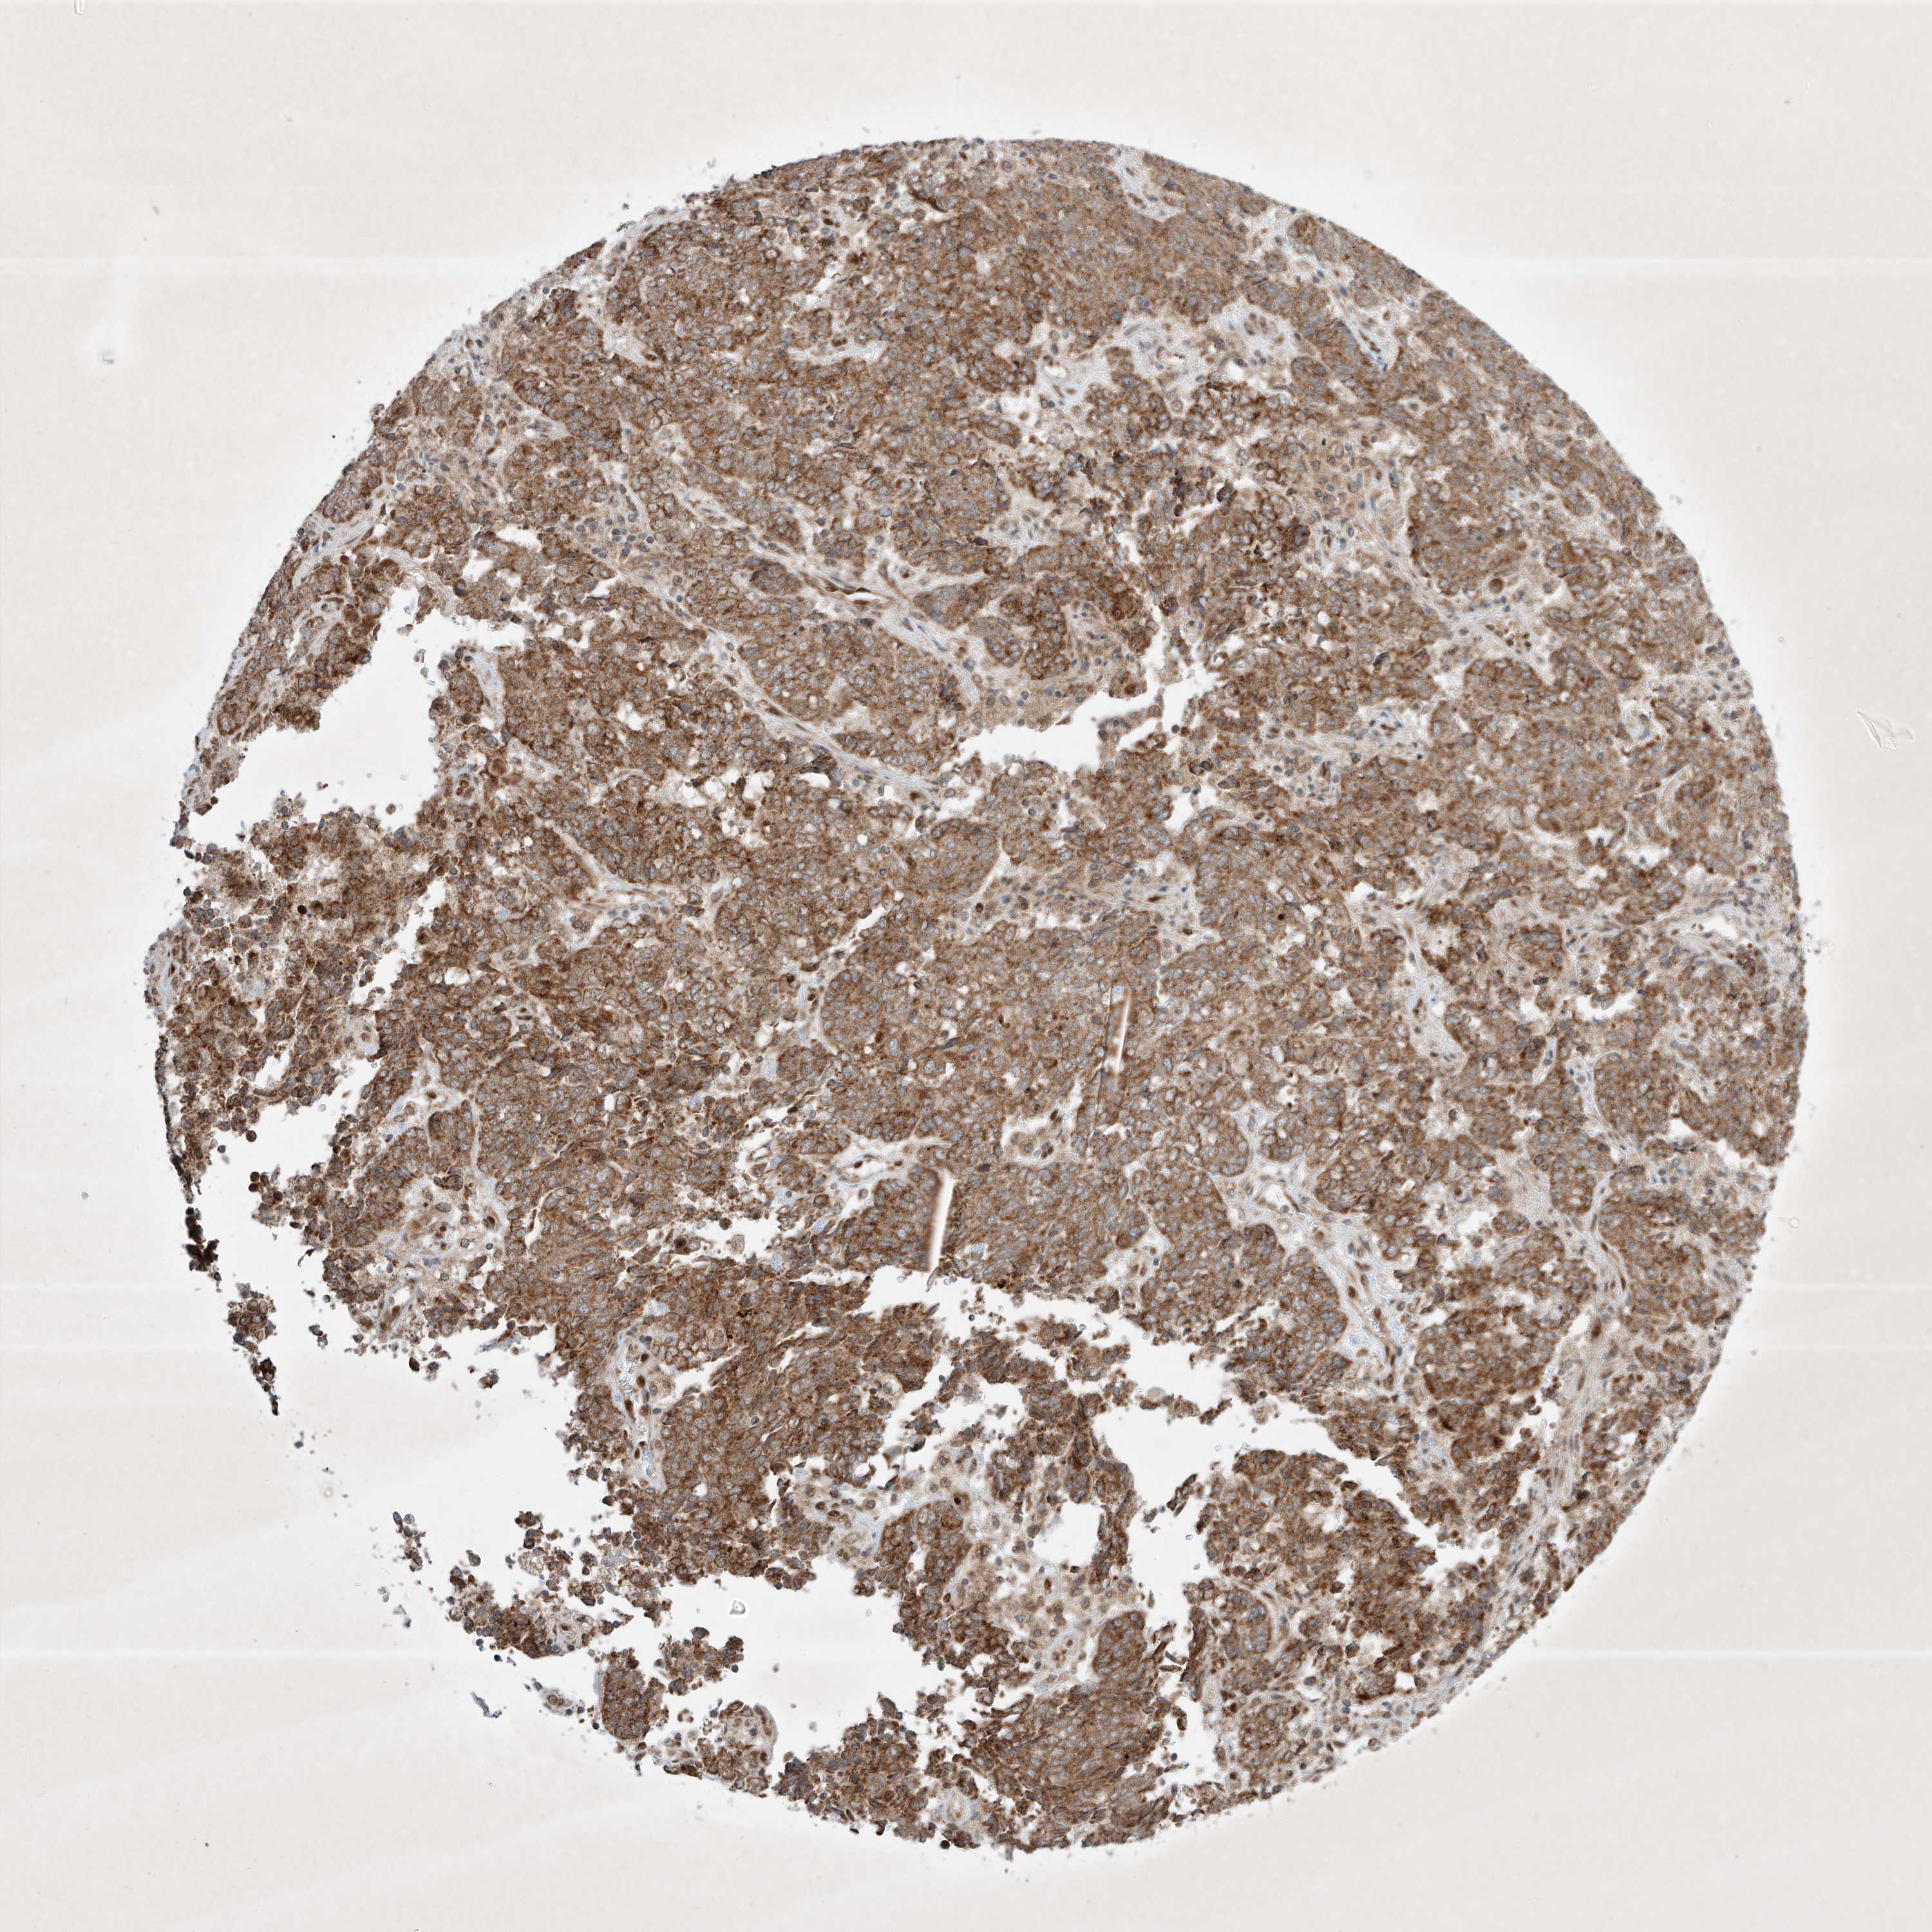

ENDOMETRIAL CANCER - Protein expressioni

A mouse-over function shows sample information and annotation data. Click on an image to view it in a full screen mode. Samples can be filtered based on level of antibody staining by selecting one or several of the following categories: high, medium, low and not detected. The assay and annotation is described here.

Note that samples used for immunohistochemistry by the Human Protein Atlas do not correspond to samples in the TCGA dataset.

Antibody stainingi

Antibody staining in the annotated cell types in the current human tissue is reported as not detected, low, medium, or high, based on conventional immunohistochemistry profiling in selected tissues. This score is based on the combination of the staining intensity and fraction of stained cells.

Each image is clickable and will lead to virtual microscopy that enables deeper exploration of all samples and also displays staining intensity scores, fraction scores and subcellular localization as well as patient and tissue information for each sample.

Antibody HPA031689

Staining

High

Medium

Low

Not detected

Intensity

Strong

Moderate

Weak

Negative

Quantity

>75%

75%-25%

<25%

None

Location

Nuclear

Cytoplasmic/membranous

Cytoplasmic/membranous,nuclear

Adenocarcinoma, NOS

Adenocarcinoma, metastatic, NOS